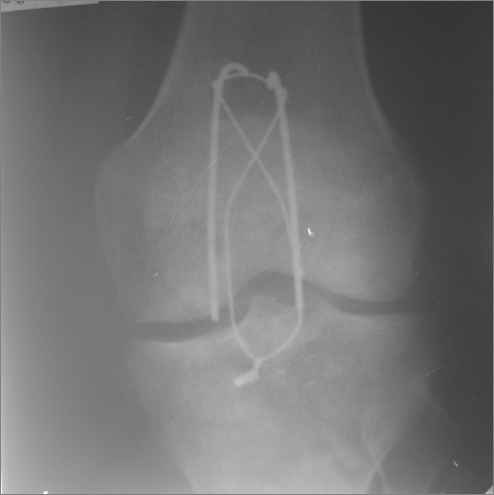

а рентгенкартинки на  пленке от 06.07.2009года  выполнены,  после разваливания  металлоконструкции.

Вложение не в текстовом формате было извлечено…

Имя     : 06.07.2009г.jpg

Тип     : image/jpeg

Размер  : 5364 байтов

Описание: отсутствует

Url     : http://weborto.net:8080/pipermail/ortho/attachments/20090710/17fd1643/attachment-0005.jpg